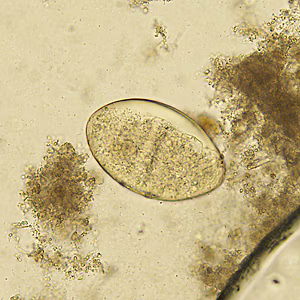

A seven-year-old boy had an ova-and-parasite (O&P) stool examination performed as part of a required refugee screening. Laboratorians at the state health department observed what they believed to be a few eggs within the size range of 110-120 micrometers. A trematode infection was suspected and images of the eggs were captured and submitted to DPDx for diagnostic assistance. The DPDx team requested that an aliquot of the concentrate be sent for further examination. Figures A–D show what was observed at 200x magnification. The objects of interest measured 115 x 72 micrometers on average. What is your diagnosis? Based on what criteria?

Figure A